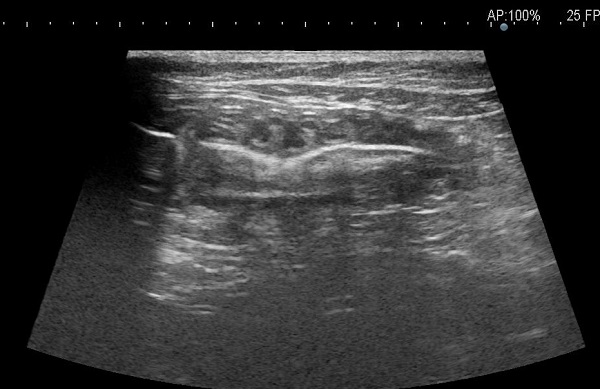

症例:和猫 2歳 雄

主訴:昨日より頻回の嘔吐

検査:エコー検査で異物を疑う腸管が確認されました。 (アコーディオン像)

治療:

開腹術により腸管から異物を摘出しました。開腹後も食事等の管理、抗生剤の投与を行い、術後合併症なども起きずに、元気になっています。

(図:取り出された異物)